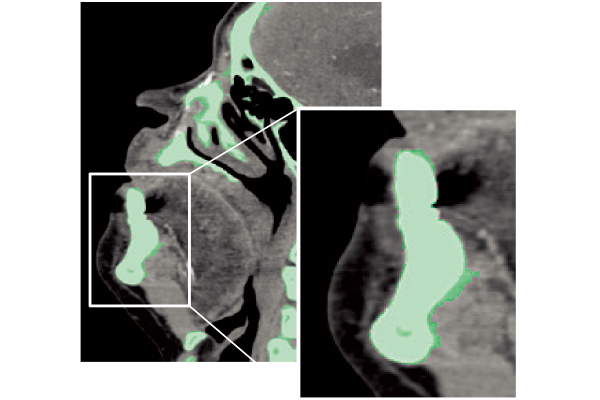

SYNAPSE 3D’s advanced image analysis technology aids clinical interpretation, reporting, and treatment planning. Especially,

automatic organ segmentation technology enables fast and effective workflow, powered by REiLI, FUJIFILM's AI brand. With

a series of high-tech applications developed in collaboration with clinical specialists, SYNAPSE 3D quickly and accurately

delivers imaging result that promotes effective care collaboration.

REiLI makes it happen to extract organs and simplify your work.

Kidney